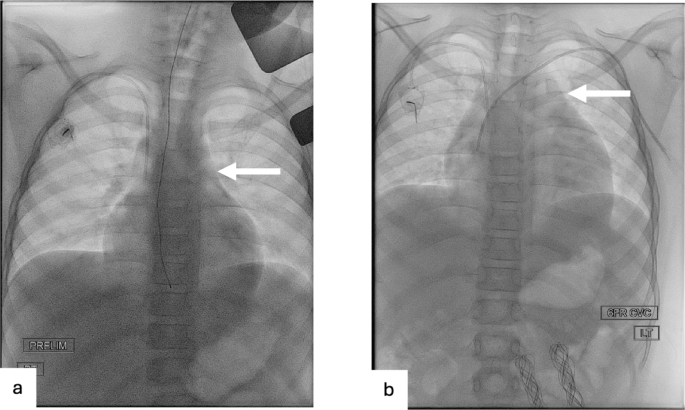

All chest CTs were reviewed by a pediatric radiologist with 8 years of experience (I.V.), who divided the patients into two groups according to the thymus size: Group 1 demonstrated a visual increase in thymus size after CAR T-cell therapy (Figs. 3 and 4). Group 2 demonstrated no change in thymus size or decreased size (i.e., no increase in thymus size) (Fig. 5). Then CT images were imported into OsiriX (Pixmeo, Bernex, Switzerland) and the thymus was outlined using the free-hand drawing tool. Automated 3D volume rendering was used to derive the volume (cm3) of the thymus (Fig s1). In addition, the same radiologist recorded the presence of lung, pleural, and mediastinal abnormalities. To complement this analysis, fluoroscopy images from interventional radiology (IR) procedures for peripherally inserted central catheter (PICC) line placement were reviewed when available. These IR fluoroscopic images, acquired at clinically relevant time points between the available chest CT and CAR T-cell infusion, provided additional reference for mediastinal silhouette and thymus size assessment. Specifically, the transverse thymic diameter was measured on these fluoroscopic chest images, allowing for comparison of thymic width before and after CAR T-cell therapy.

Fluoroscopic chest images from interventional radiology (IR) procedures of a 12-year-old male patient with B-ALL before and after CAR T-cell therapy. a) Frontal fluoroscopic chest image acquired during PICC line placement demonstrates a normal mediastinal contour with no evidence of thymic enlargement. b) Frontal fluoroscopic image at 32 days post-CAR T-cell shows increased prominence of the anterior mediastinal silhouette, suggesting interval thymic enlargement.